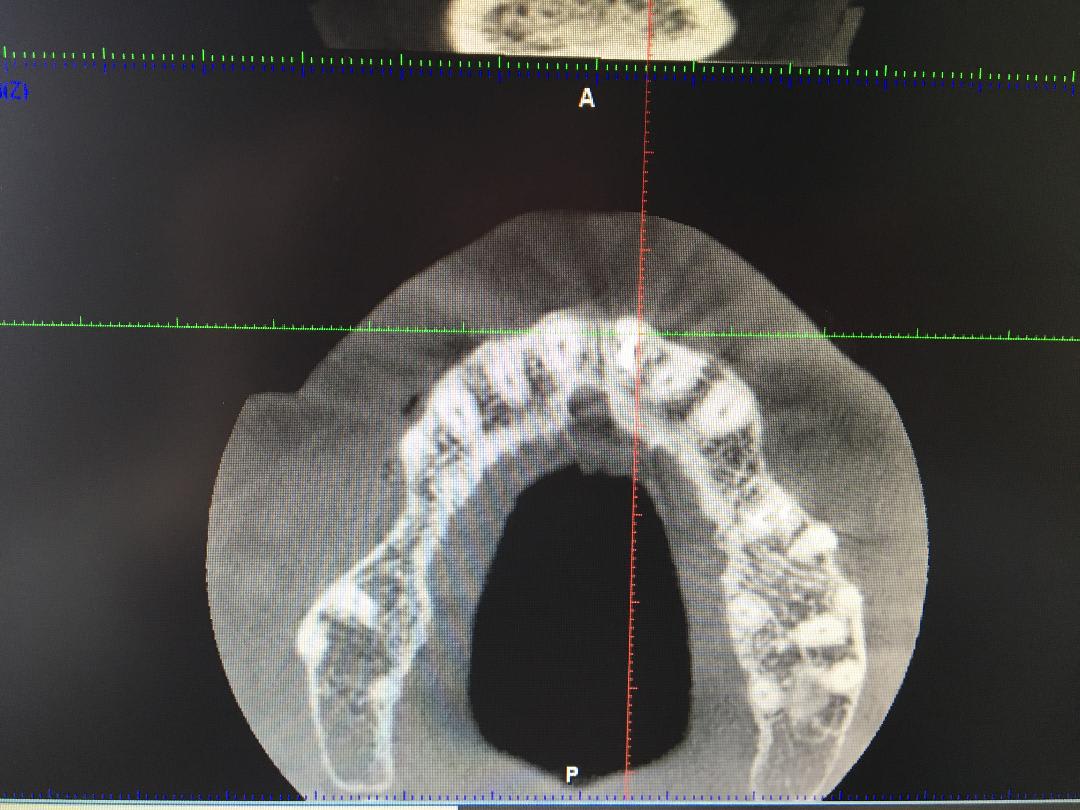

comment s'assurer que le remplacement d'une 11 à extraire et présentant un collet gingival plus haut que les autres incisives pourra se faire avec un implant en rétablissant cet alignement gingival sur la couronne implantaire ?

depuis la dent a été extraite

avant avulsion

21